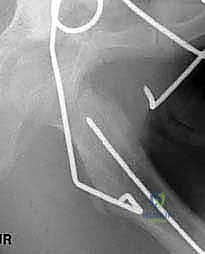

3. إدخال سلك الدليل (Guide Wire Placement)

هذه هي الخطوة الأكثر أهمية. باستخدام الأشعة المباشرة، يقوم الدكتور بإدخال سلك معدني رفيع في عنق عظم الفخذ باتجاه الرأس. يتم وضع هذا السلك بزاوية محسوبة مسبقاً بدقة متناهية لتتطابق مع زاوية الشريحة (90 درجة).

4. تحضير مسار الشريحة النصلية (Seating Chisel)

باستخدام أداة خاصة تشبه الإزميل، يتم حفر مسار دقيق داخل العظم الإسفنجي لعنق الفخذ، وذلك تمهيداً لإدخال نصل الشريحة المعدنية.

6. إدخال الشريحة والتثبيت (Plate Insertion & Fixation)

يتم إدخال نصل الشريحة ذات الزاوية 90 درجة في المسار الذي تم تحضيره في عنق الفخذ. ثم يتم ضم جزئي العظم المقطوعين معاً (إغلاق الفجوة)، مما يؤدي فوراً إلى تغيير زاوية عنق الفخذ إلى الوضع الطبيعي الجديد. يتم تثبيت الجزء الطويل من الشريحة على جسم عظم الفخذ باستخدام براغي قوية من التيتانيوم أو الفولاذ الطبي المقاوم للصدأ.

لماذا الشريحة ذات الزاوية 90 درجة (90-Degree Blade Plate) تحديداً؟

قد يتساءل البعض: لماذا يصر الأستاذ الدكتور محمد هطيف على استخدام هذا النوع المحدد من الشرائح في عمليات قطع عظم الفخذ الداني التقويمي؟ الإجابة تكمن في الميكانيكا الهندسية:

- التثبيت فائق الصلابة (Rigid Fixation): النصل العريض للشريحة الذي يدخل في عنق الفخذ يوفر ثباتاً دورانياً وزاوياً لا مثيل له، مما يمنع العظمة من التحرك أثناء فترة الالتئام.

- التحكم الدقيق في الزوايا ثلاثية الأبعاد: تسمح هذه الشريحة بتصحيح زاوية الميل (Varus)، وكذلك تصحيح الدوران الخاطئ للعظمة (Derotation) في نفس الوقت.